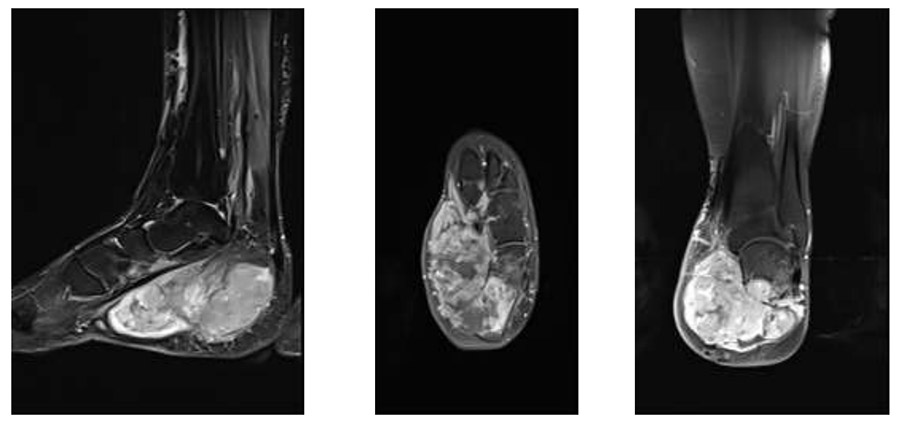

Ameliyat Öncesi: MR’da kalkaneusta ciddi harabiyete neden olan sınırları düzensiz, heterojen büyük yumuşak doku kitlesi görülmekte